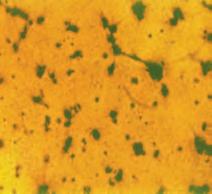

Rysunek na sąsiedniej stronie przedstawia przekrój mikroskopowy wątroby pacjenta chorującego na białaczkę limfatyczną.

Każda z małych fioletowych kropek widocznych na zdjęciu to pojedyncza biała krwinka (w tym przypadku limfocyt), która zaatakowała tkankę wątroby (obszar w kolorze różowym).

Zważywszy na wielką liczbę tych fioletowych kropek oraz produkowane przez nie ilości enzymów trawiących kolagen, łatwo sobie wyobrazić, jak wielkie mogą być uszkodzenia tkanki łącznej oraz wyniszczenie organu, spowodowane tym typem raka.

Zdjęcie mikroskopowe białaczki limfatycznej.